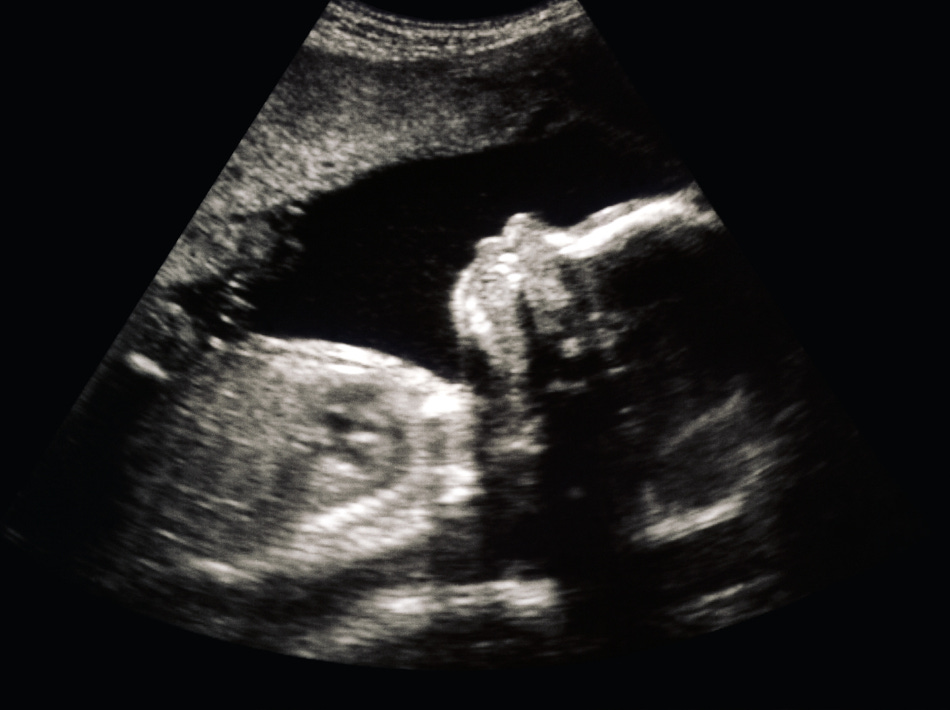

On one side, it had a picture of an 8-week-old unborn baby. You could clearly see the hands and feet of the child; you could even count fingers and toes. It was a beautiful picture, but it was the second picture that caught my attention — and changed my life forever.